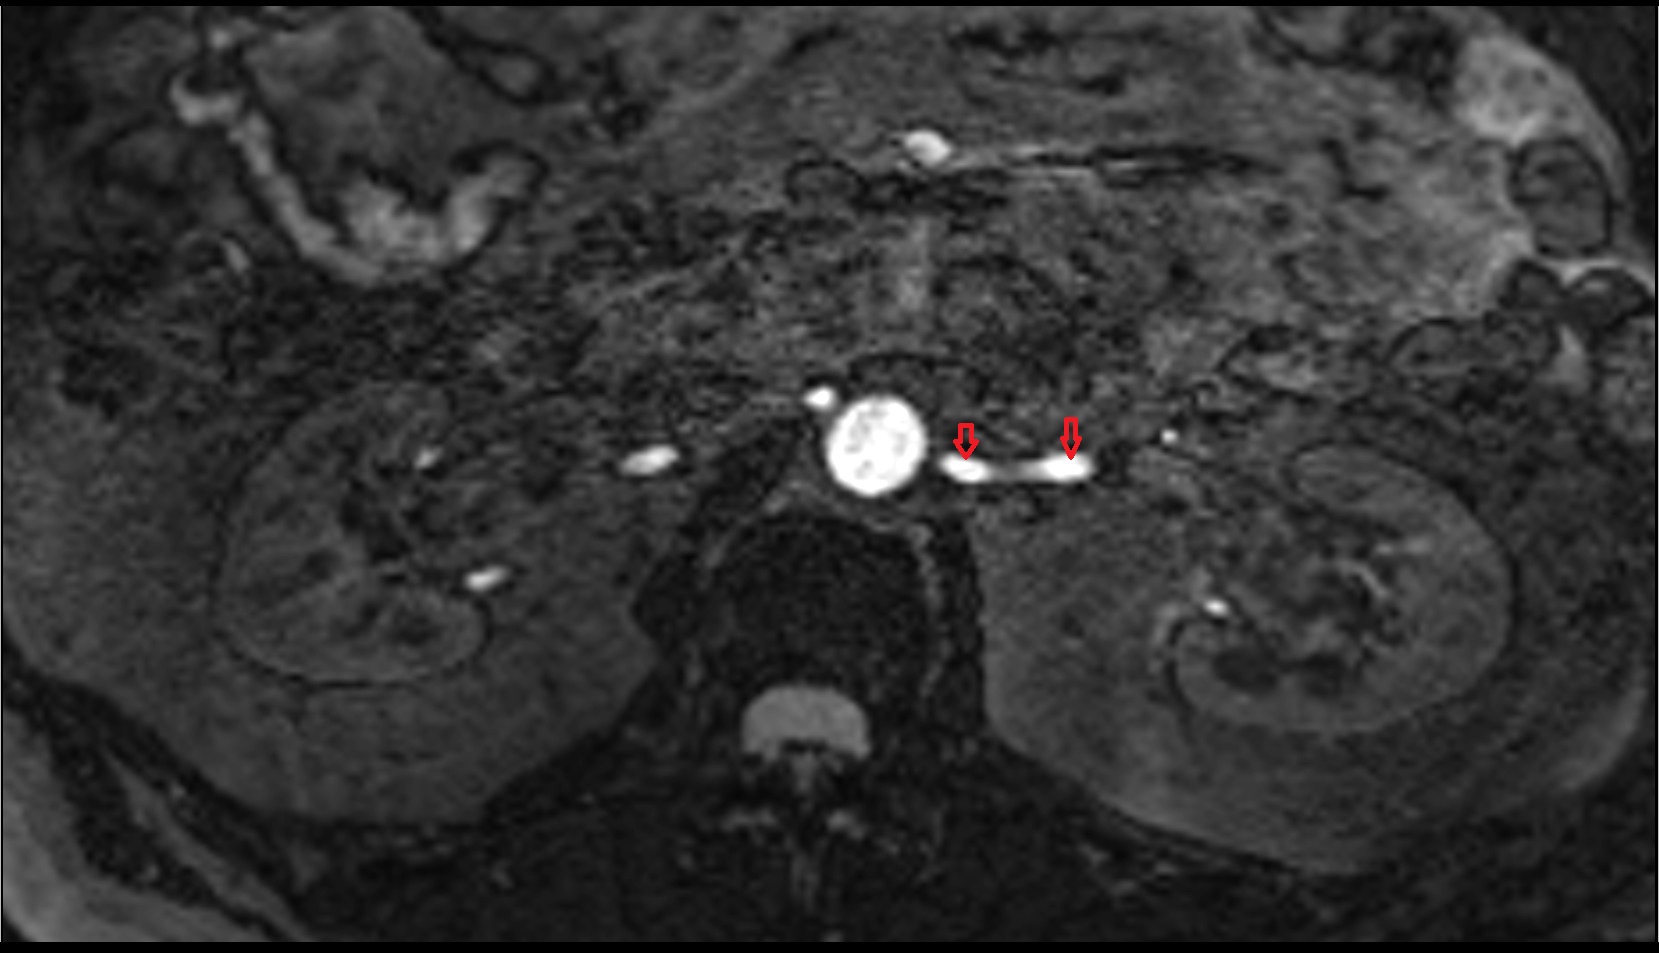

- Renal artery

- Left renal vein

- Left renal artery

- Right renal artery